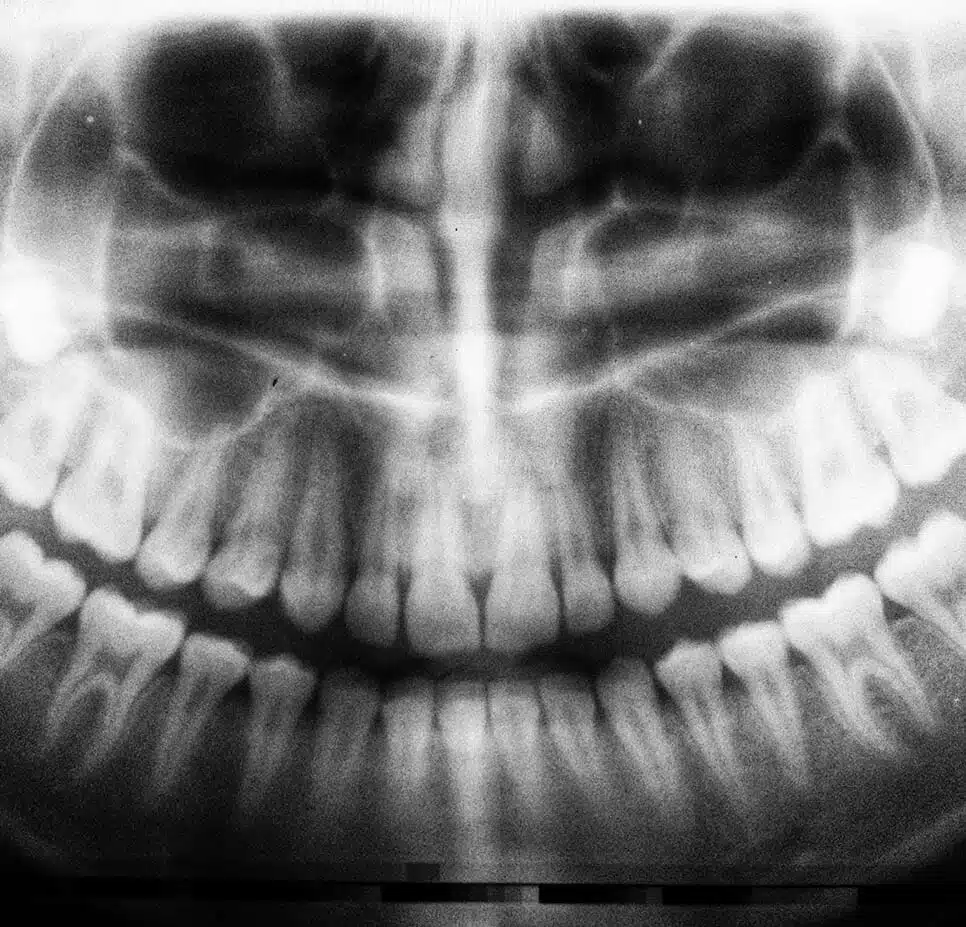

Going to the dentist on a regular basis might not be the most exciting thing we do in life, but it’s vital for preventing gum disease and tooth decay. Luckily, at Clarity Dental we offer a variety of preventive dental services, from teeth cleaning to x-rays and exams. Visiting us every 6 months results in easier, less stressful, less expensive, encounters.